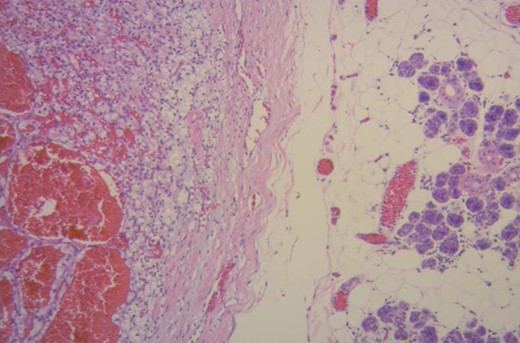

The histopathological analysis of the right submandibular gland informed: tumor proliferation composing atypical epithelial cells with pleomorphic, hyperchromatic nuclei with prominent nucleoli and clear cytoplasm. They were arranged forming nests and acini surrounded by a delicate fibrovascular network, with areas of hemorrhage with deposits of hemosiderin and stroma with hyaline degeneration. The lesion invaded the submandibular gland (Fig. 2). The results confirmed an RCCC origin.

Renal clear cell carcinoma metastasis to submandibular gland (right). Submandibular glandular parenchyma with a well circumscribed tumor (left) composed of an alveolar, tubular and cystic, clear cell tumor with distinct but delicate cell boundaries and a characteristic network of small, thin walled vasculature. (Hematoxylin–eosin ×100.)